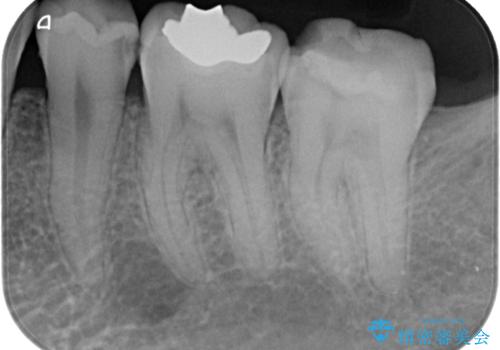

- 詰め物が欠けて虫歯になっていることを気にして来院された患者様です。以前に保険のプラスチックの治療を行われていた状況でした。

歯と歯が接しているところの虫歯のため、セラミックの詰め物(セラミックインレー)での治療を進めていくことにしました。

拡大鏡視野下で、保険のプラスチック、虫歯の除去を行い、セラミックインレーに適した形に整えました。

歯と歯の間の虫歯をコンポジットレジンや保険のメタルインレーで治すと段差ができたりして清掃性が悪くなるので、セラミックインレー修復やゴールドインレー修復などの適合の良い詰め物で治療することをオススメします。